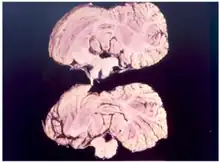

Kuru is a rare, incurable, and fatal neurodegenerative disorder that was formerly common among the Fore people of Papua New Guinea. Kuru is a form of transmissible spongiform encephalopathy (TSE) caused by the transmission of abnormally folded proteins (prions), which leads to symptoms such as tremors and loss of coordination from neurodegeneration.

Kuru, a transmissible spongiform encephalopathy, is a disease of the nervous system that causes physiological and neurological effects which ultimately lead to death. It is characterized by progressive cerebellar ataxia, or loss of coordination and control over muscle movements.[11][12]

In the terminal stage, the infected individual's existing symptoms, like ataxia, progress to the point where it is no longer possible to sit up without support. New symptoms also emerge: the individual develops dysphagia, which can lead to severe malnutrition, and may also become incontinent, lose the ability or will to speak, and become unresponsive to their surroundings despite maintaining consciousness.[14] Towards the end of the terminal stage, patients often develop chronic decubitus ulcerated wounds that can be easily infected. An infected person usually dies within three months to two years after the first terminal stage symptoms, often because of aspiration pneumonia[15] or other secondary infections.[16]